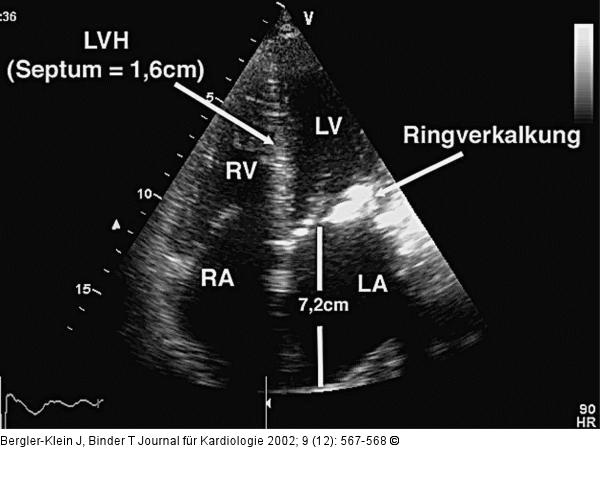

Abbildung 2: Mitralklappen - Ringverkalkung Apikaler Vierkammerblick: deutliche linksventrikuläre Hypertrophie (LVH) und ausgeprägte Ringverkalkung (lateral). Der linke Vorhof (LA) ist mit 7,2 cm im Längsdurchmesser deutlich vergrößert (LV = linker Ventrikel, RV = rechter Ventrikel, RA = rechter Vorhof). |

Apikaler Vierkammerblick: deutliche linksventrikuläre Hypertrophie (LVH) und ausgeprägte Ringverkalkung (lateral). Der linke Vorhof (LA) ist mit 7,2 cm im Längsdurchmesser deutlich vergrößert (LV = linker Ventrikel, RV = rechter Ventrikel, RA = rechter Vorhof). |